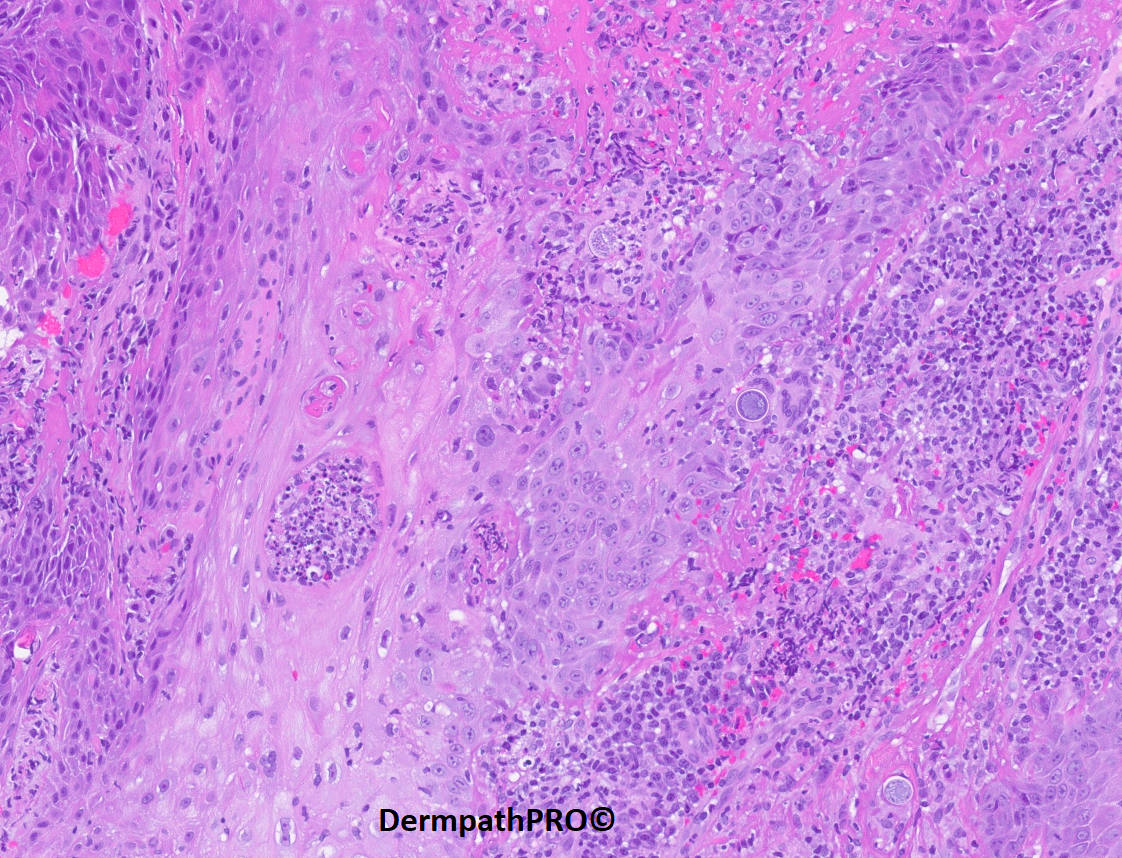

51 year-old male who has been developing large crusted ulcerative lesions starting on wrists, later spreading to the chest. Patient recalls cleaning a very dirty porch some time prior to developing these.